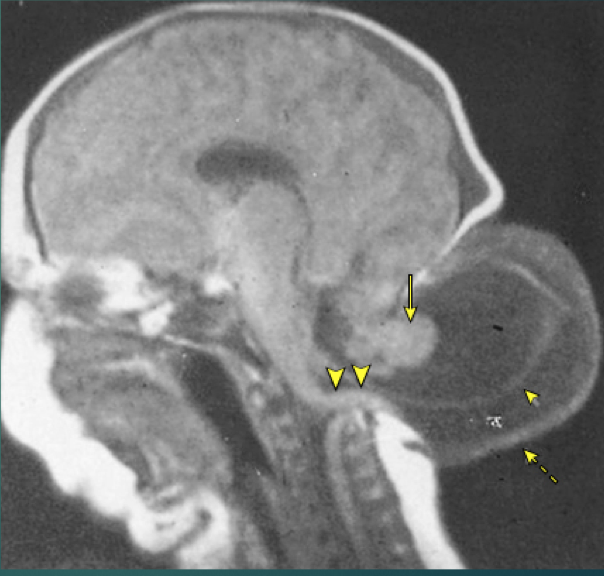

Describe the differences of Chiari Type I, II, and III malformations.

Chiari type I is congenital extension of the cerebellar tonsils through the formamen magnum (by 5mm or more) which can cause obstruction of CSF flow -> hydrocephalus

Chiari type II is the same thing as type I plus there is a myelomeningocele

Chiari type III is herniation of the cerebellar tonsils plus a myelomeningocele at the foramen magnum; they are associated with anencephaly

What is your Dx?

Chiari type III malformation (myelomeningocele at the foramen magnum)